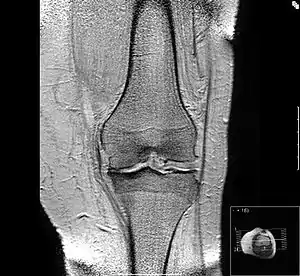

Остеоартро́з (новолат. osteoarthrosis, від грец. το οστεον — кістка, το αρθρον — суглоб; синоніми: деформуючий остеоартроз (ДОА), артроз, деформаційний артроз) — дистрофічне захворювання суглобів, яке розвивається через дегенерацію суглобового хряща.